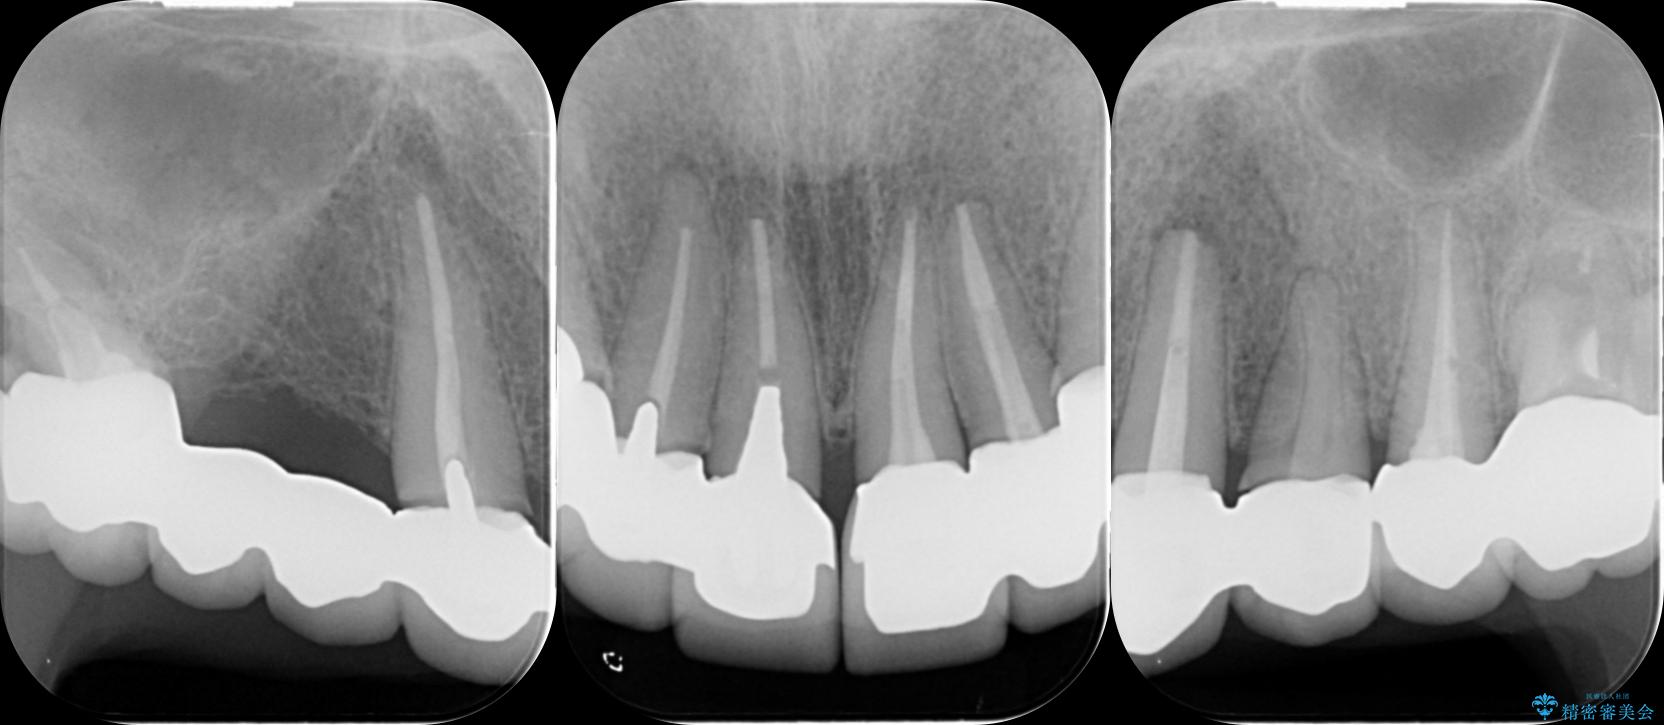

歯周組織検査を行うと歯ぐきからは容易に出血し、X線検査より歯とセラミッククラウンの適合が悪い(ピッタリと合っていない)状態が示唆され、歯ぐきの炎症を惹起している状態でした。